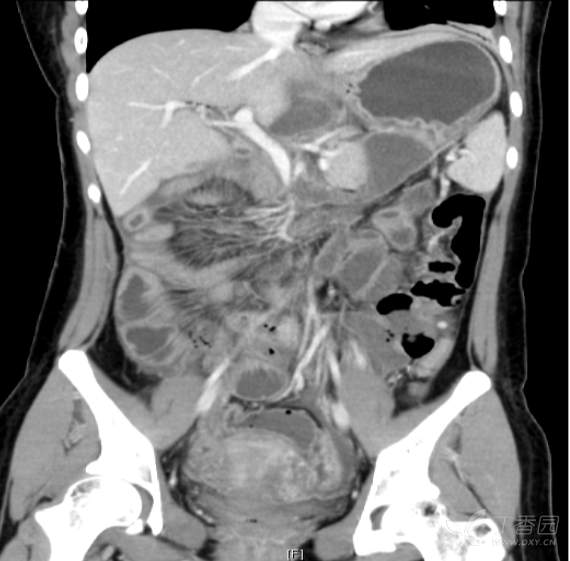

然后就是切除右半结肠,最后行胰肠吻合、胆肠吻合、胃肠吻合。手术历时12小时,出血300ml,下图是术后病理报告截图和出院前复查增强CT。